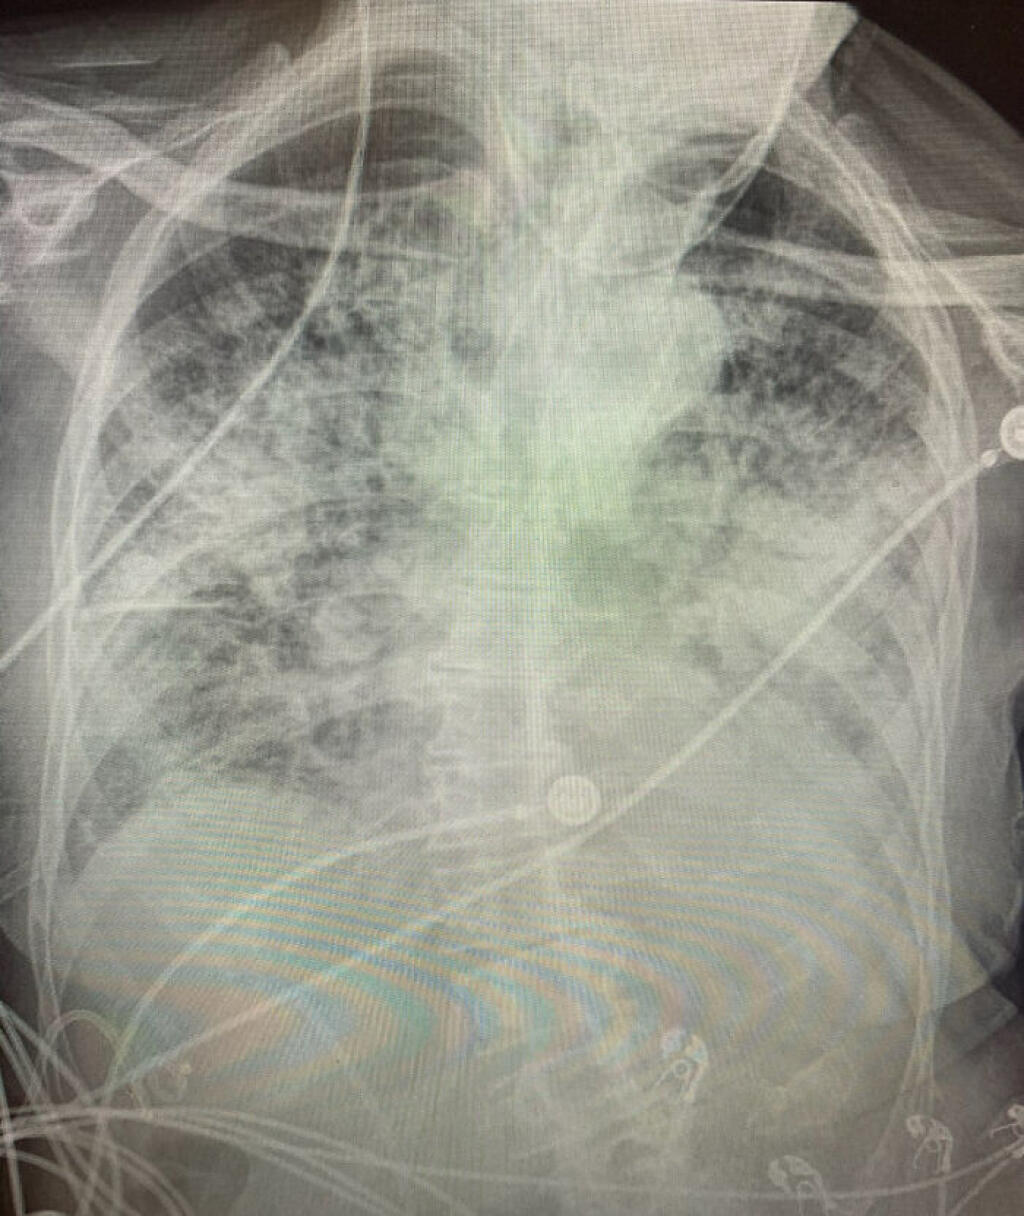

Поражение легких является одним из основных симптомов коронавируса (COVID-19). В данной статье представлены фото рентгеновских снимков, которые позволяют визуально оценить состояние легких при этом заболевании.

На фотографиях рентгеновских снимков видно, как вирус воздействует на легочную ткань. Характерные признаки поражения легких включают пятна, инфильтраты и наличие жидкости внутри легочных альвеол.

Фото рентгеновских снимков помогают врачам и специалистам визуально определить степень поражения легких и принять соответствующие меры лечения и поддержки пациента.